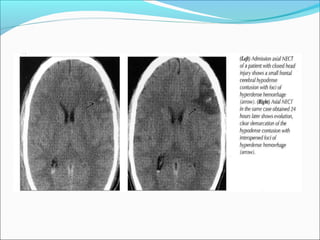

SUBDURAL HEMATOMA

ļ‚—hyperdense(acute), isodense(subacute)

Hypodense(chronic),

Radiological signs

ļ‚—Crescent shape

ļ‚—The most common locations are the frontal and

parietal convexities.

ļ‚—Countercoup

ļ‚—Unlike an EDH, its spread is not limited by suture

lines; it can spread over the whole convexity, but it

almost never crosses the midline

ļ‚—Mass effect +/-brain herniation

ļ‚—Skull fracture in < 50 %